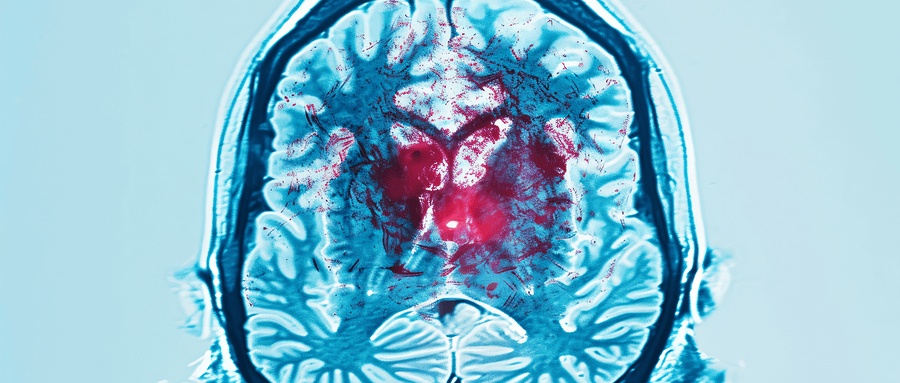

【综述】颅内动脉瘤滋养血管的研究进展

该文从滋养血管对血管壁的生理作用、颅内动脉滋养血管的分布、颅内动脉瘤滋养血管的临床意义以及影响颅内动脉瘤滋养血管的可能因素4 方面进行综述,以期为临床干预颅内动脉瘤滋养血管的发生提供思路。